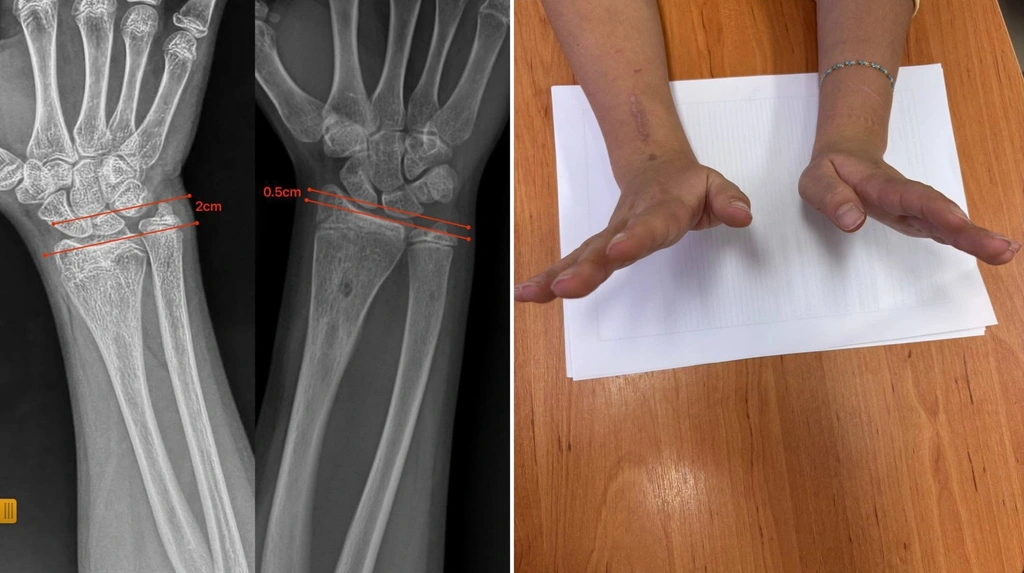

Через сім місяців форма передпліччя повністю нормалізувалася, ріст кістки відбувається правильно, а функція кінцівки збережена у повному обсязі.

У лікарні зазначають, що цей випадок демонструє: не всі деформації потребують складних операцій. Іноді достатньо усунути причину, яка блокує ріст кістки, щоб вона знову почала розвиватися природним шляхом.